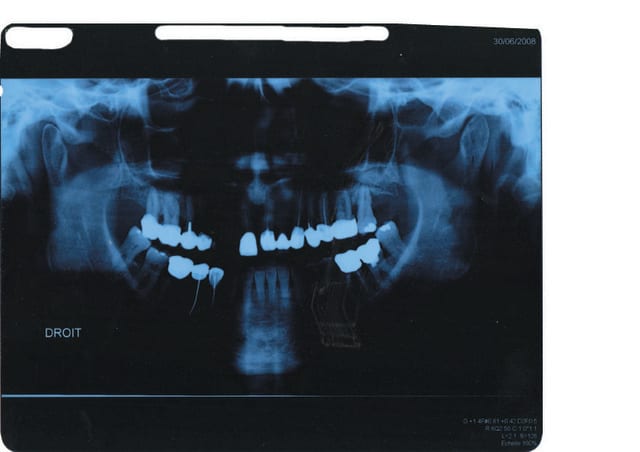

je viens de recevoir une patiente qui va se faire poser une prothèse de hanche dans 2 mois.

Dans un temps aussi court est-ce qu'il vous parait

possible de remettre en état sans pratiquer des extractions multiples, les endos sur 15 et 47 sont pratiquement inexistantes , bridge sur dents vivantes , tout est assymptomatique, 48?

désolée ... voici les radios